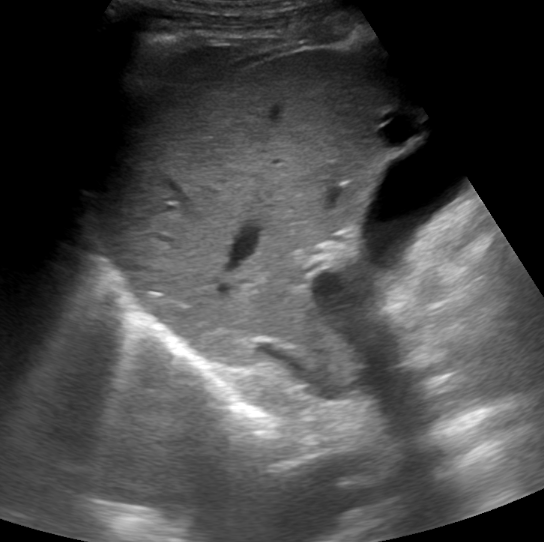

Ecografía: La vena Cava Inferior muestra un claro artefacto de refuerzo acústico posterior

Vejiga con refuerzo acústico posterior en corte suprapúbico

Corte suprapúbico de vejiga mostrando refuerzo acústico posterior característico